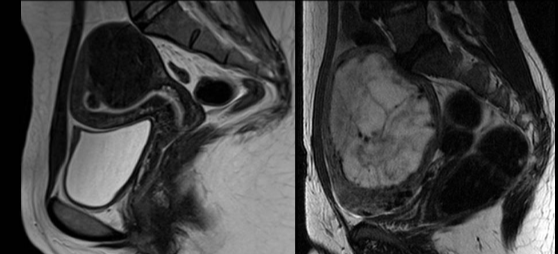

| 术前 | 术后 |

因子宫肌瘤接受磁共振聚焦超声治疗的患者的治疗前后 CE-T1W 磁共振成像图像。 治疗结束后立即进行增强型磁共振成像检查,结果显示存在未灌注区域。

消融区域坏死周边,残留的部分好像不少,会不会是MRgFUS 再干预机会大的原因